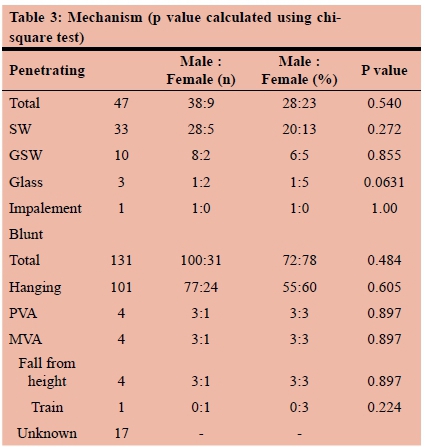

RESULTS: During the five-year study period, a total of 179 patients were included. The mean age was 29 years (SD12) and there were 139 (77%) males and 40 (23%) females. Of these, 16 had a previously established psychiatric diagnosis and two had a prior history of having sustained self-harm. The previously diagnosed psychiatric illnesses included mood dysphoria disorders (5), schizophrenia (3), substance abuse and dependency (1), anti-social personality disorder (1) and unspecified (6). The mechanism was penetrating trauma in 47 (26%). The penetrating mechanisms included stab wounds (SW) in 33, gunshot wounds (GSW) in 10, broken glass in 2 and a single impalement. Blunt mechanisms accounted for the remaining 131 (73%) injuries. The most common mechanism of blunt self-harm was hanging in 101 patients. This was followed by vehicular related trauma (8), jumping in front of a train (1) and jumping from a height (1). In 17 patients the exact mechanism of the blunt trauma was unclear. There was no statistical difference in the mechanism of injury between male and female patients. There were 38 (28%) men and 9 (23%) women who sustained a penetrating injury and there were 100 (72%) male and 31 (78%) female patients who had a blunt mechanism of injury. A total of 53 CT scans were obtained, 40 chest X-rays, 9 abdominal X-rays and 2 ultrasounds. There were 113 neck injuries, 68 head injuries, 24 abdominal injuries, 15 upper limb and 15 lower limb injuries and four facial injuries. A total of 32 operations were performed. These included laparotomy (14), neck exploration (5), tracheostomy (4). A total of 22 patients developed a complication

The mechanism was penetrating trauma in 47 (26%). The penetrating mechanisms included stab wounds (SW) in 33, gunshot wounds (GSW) in 10, broken glass in 2 and a single impalement. Figure 1 shows a self-inflicted wound of the neck and Figure 2 shows the CT scan of a suicide victim who attempted to shoot himself in the head. Blunt mechanisms accounted for the remaining 131 (73%) injuries. The most common mechanism of blunt self-harm was hanging in 101 patients. This was followed by vehicular related trauma in (8), jumping in front of a train in (1) and jumping from a height in (1). In 17 patients, the exact mechanism of the blunt trauma was unclear. There was no statistical difference in the mechanism of injury between male and female patients. There were 38 (28%) men and 9 (23%) women who sustained a penetrating injury and there were 100 (72%) male and 31 (78%) female patients who had a blunt mechanism of injury. Table 3 summarizes the mechanisms of injury according to sex.

Interventions